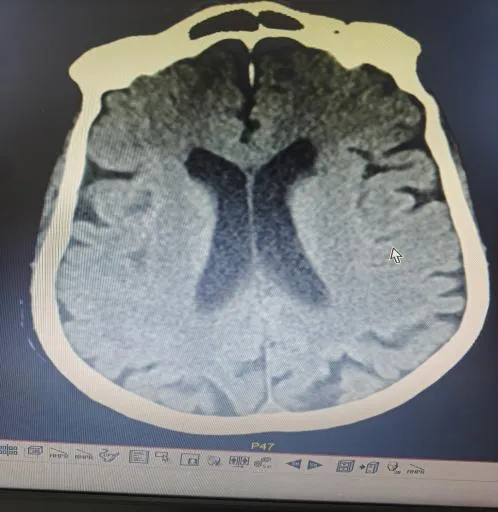

“时间就是大脑,每延迟一分钟,就有190万个神经细胞不可逆坏死!”面对紧急病情,医护团队争分夺秒。快速完成头颅CT等检查后,明确患者符合静脉溶栓指征且无绝对禁忌证,与家属协商签署溶栓同意书后,于22:04立即对患者进行阿替普酶溶栓治疗,DNT时间仅34分钟。然而,溶栓后复查影像学显示,患者大脑中动脉主干仍大血管闭塞,单纯溶栓未彻底开通血管,病情高危。关键时刻,救治团队当机立断,决定采用当前急性大血管闭塞性脑卒中的前沿救治方案——“溶栓桥接取栓”,为患者打通生命通道。

手术室内,神经内科张奕主任凭借丰富经验和精湛技术,在数字减影血管造影机引导下,经毫米级微创通道,将取栓器械精准送达闭塞血管核心部位。经不到1小时操作,成功完整取出堵塞血管的栓子,闭塞血管再通,脑部血供恢复。术后复查头颅 CT显示低灌注区脑组织全部存活。